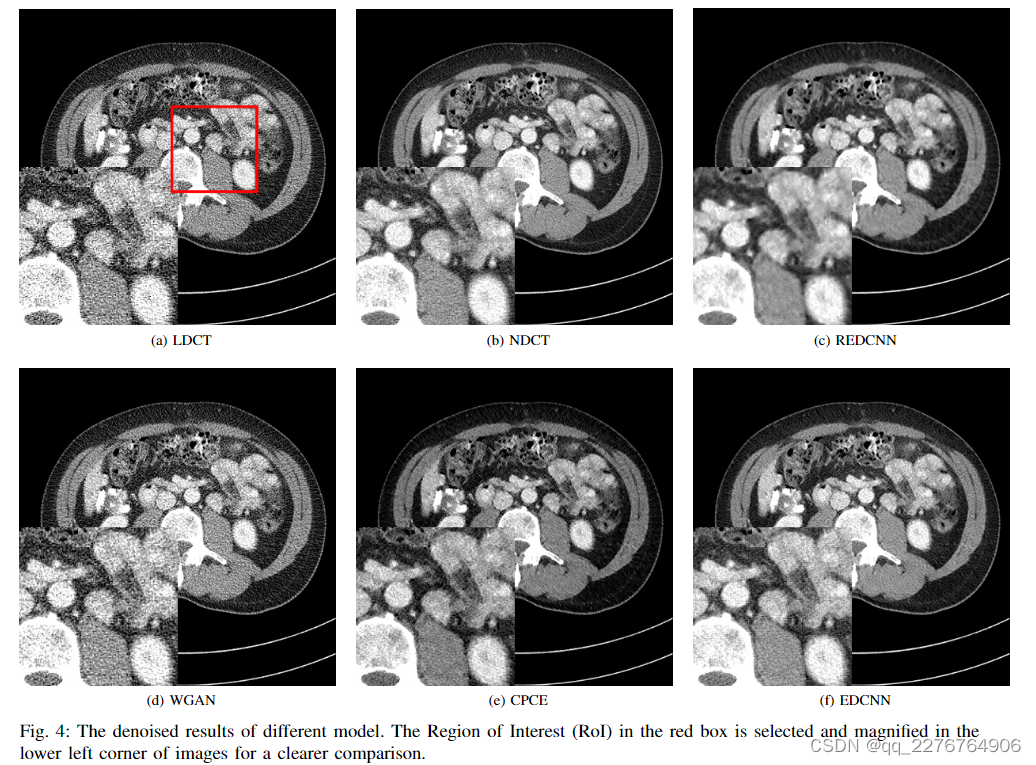

由于PSNR和RMSE的计算过程与MSE直接相关,因此仅使用MSE作为损失函数训练的模型就可以在这些指标上获得良好的结果。 但这些标准并不能真实反映输出图像的视觉质量,因此只能作为相对参考。 为了比较去噪结果,如图4所示,我们选择具有复杂结构的CT图像来显示这些模型的性能。 我们可以注意到,LDCT 图像(图 4a)中的噪声比 NDCT 图像(图 4b)中的噪声更多。 对 LDCT 图像进行去噪后,REDCNN 的输出(图 4c)明显过度光滑

虽然它具有最高的PSNR和最低的RMSE,但图像的视觉感受不佳,存在图像模糊和结构细节丢失的问题。 WGAN和CPCE都是基于Wasserstein GAN,具有感知损失和对抗性损失。 图4d为WGAN的去噪CT图像,其保留了原始图像的结构信息,但其对噪声的抑制仍然比较差。 如图 4e 和图 4f 所示,CPCE 模型和我们的 EDCNN 具有相当的性能。 它们的输出图像都与目标NDCT图像非常相似(图4b),保留了CT图像的微妙结构。 但从噪点的细节来看,我们还是可以注意到它们之间的区别。 EDCNN比CPCE具有更好的降噪性能,这也与表1中指标的值一致。